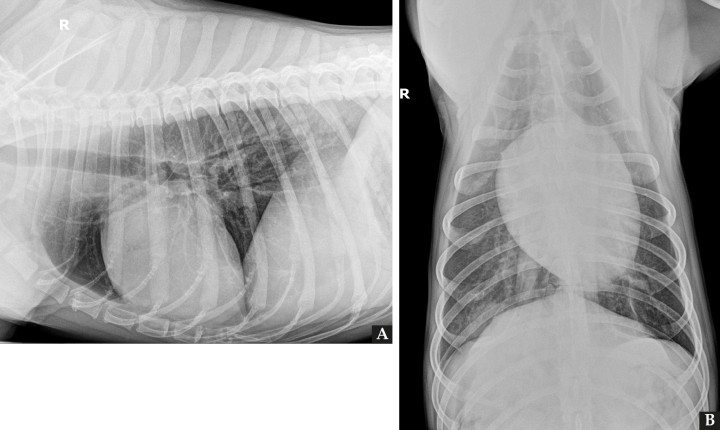

Se presenta un labrador hembra esterilizada de 6 años a mediados del mes de agosto en la región de Madrid, con historial de fiebres recurrentes de 15 días de evolución a la cual se le realizaron pruebas de enfermedades infecciosas transmitidas por vectores (Ehrlichia, Anaplasma, Filaria y Leishmania) con resultados negativos. Se administró antibioterapia de amplio espectro y antiinflamatorios no esteroideos y las fiebres cesaron puntualmente. Su centro veterinario la remitió porque al terminar el tratamiento la paciente volvió a mostrar decaimiento y fiebre de 39,7 ºC. Analíticamente presentaba leucocitosis neutrofílica severa (30,96 x 109/l; RR: 6,00-17,00 x 109/l) y un panel bioquímico sin alteraciones reseñables. Se realizó proteína C reactiva con valor superior a 150 mg/dl (RR: 1-10 mg/dl). Se realizó estudio ecográfico abdominal que no presentaba alteraciones. Se realizó un estudio radiográfico de tórax con proyecciones lateral derecha y ventrodorsal (Fig. 1).

<p>Radiografías de tórax de la paciente en proyección lateral derecha (<strong>A</strong>) y ventrodorsal (<strong>B</strong>). Fallo en la técnica: Presencia de la letra indicativa del decúbito en superposición con la paciente.</p>

Radiografías de tórax de la paciente en proyección lateral derecha (A) y ventrodorsal (B). Fallo en la técnica: Presencia de la letra indicativa del decúbito en superposición con la paciente.